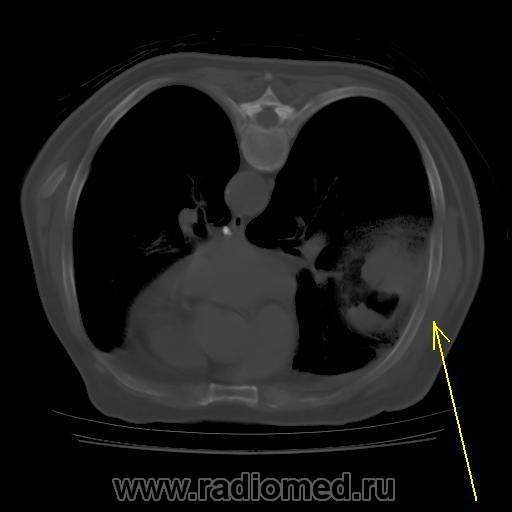

И возникла совершенно шальная мысль. А где располагается "ЭТО"? В легочной ткани или нет? и умозрительное продолжение контуров "ЭТОГО", показало, что "ЭТО" выходит за пределы грудной клетки, а именно костных её компонентов, что находит подтверждение на отдельных сканнах.

А не экстраплевральная - ли "ЭТО" пломба, которая была применена по типу "олеоторакса"?